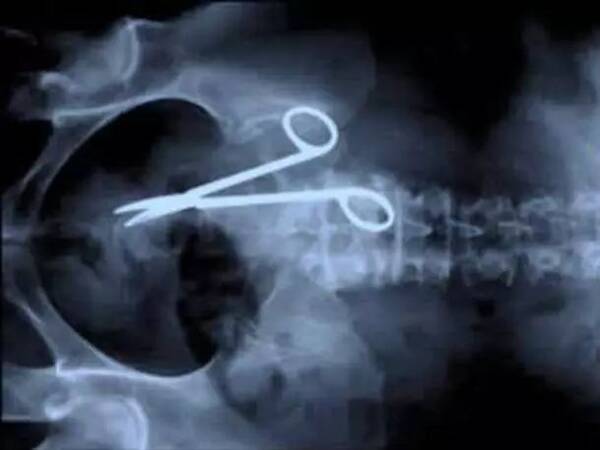

一些奇奇怪怪的x光片,看得整个人都不好了

子宫x光片

妇科盆腔x光片

盆腔x光片